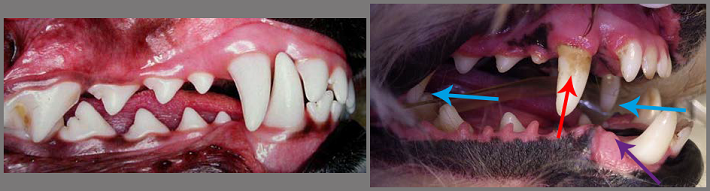

Hieronder zie je het gebit (bovenkaak) van een Bordercollie naast dat van een brachycefale Mopshond.

Er is een lange lijst afwijkingen te noemen van het gebit bij kortsnuiten. Kijk eerst eens naar het verschil tussen de foto van een hond met een mooie sluiting van de kaak, en die van de sluiting van een hond met een te korte bovenkaak. Bij de gezonde kaak past alles keurig in elkaar, er is nergens frictie. De bek kan dicht, het gebit is schoon, er is geen tandvleesontsteking. Bij de kortsnuit kan de bek niet dicht, waardoor kauwen heel moeilijk of onmogelijk is. Tussen de tanden zijn abnormale contacten (blauwe pijlen). Bovendien valt de onderlip over enkele kiesjes naar binnen, achter de hoektand (paarse pijl). Er is tandvlees ontsteking zichtbaar en tandplaque (rode pijl).